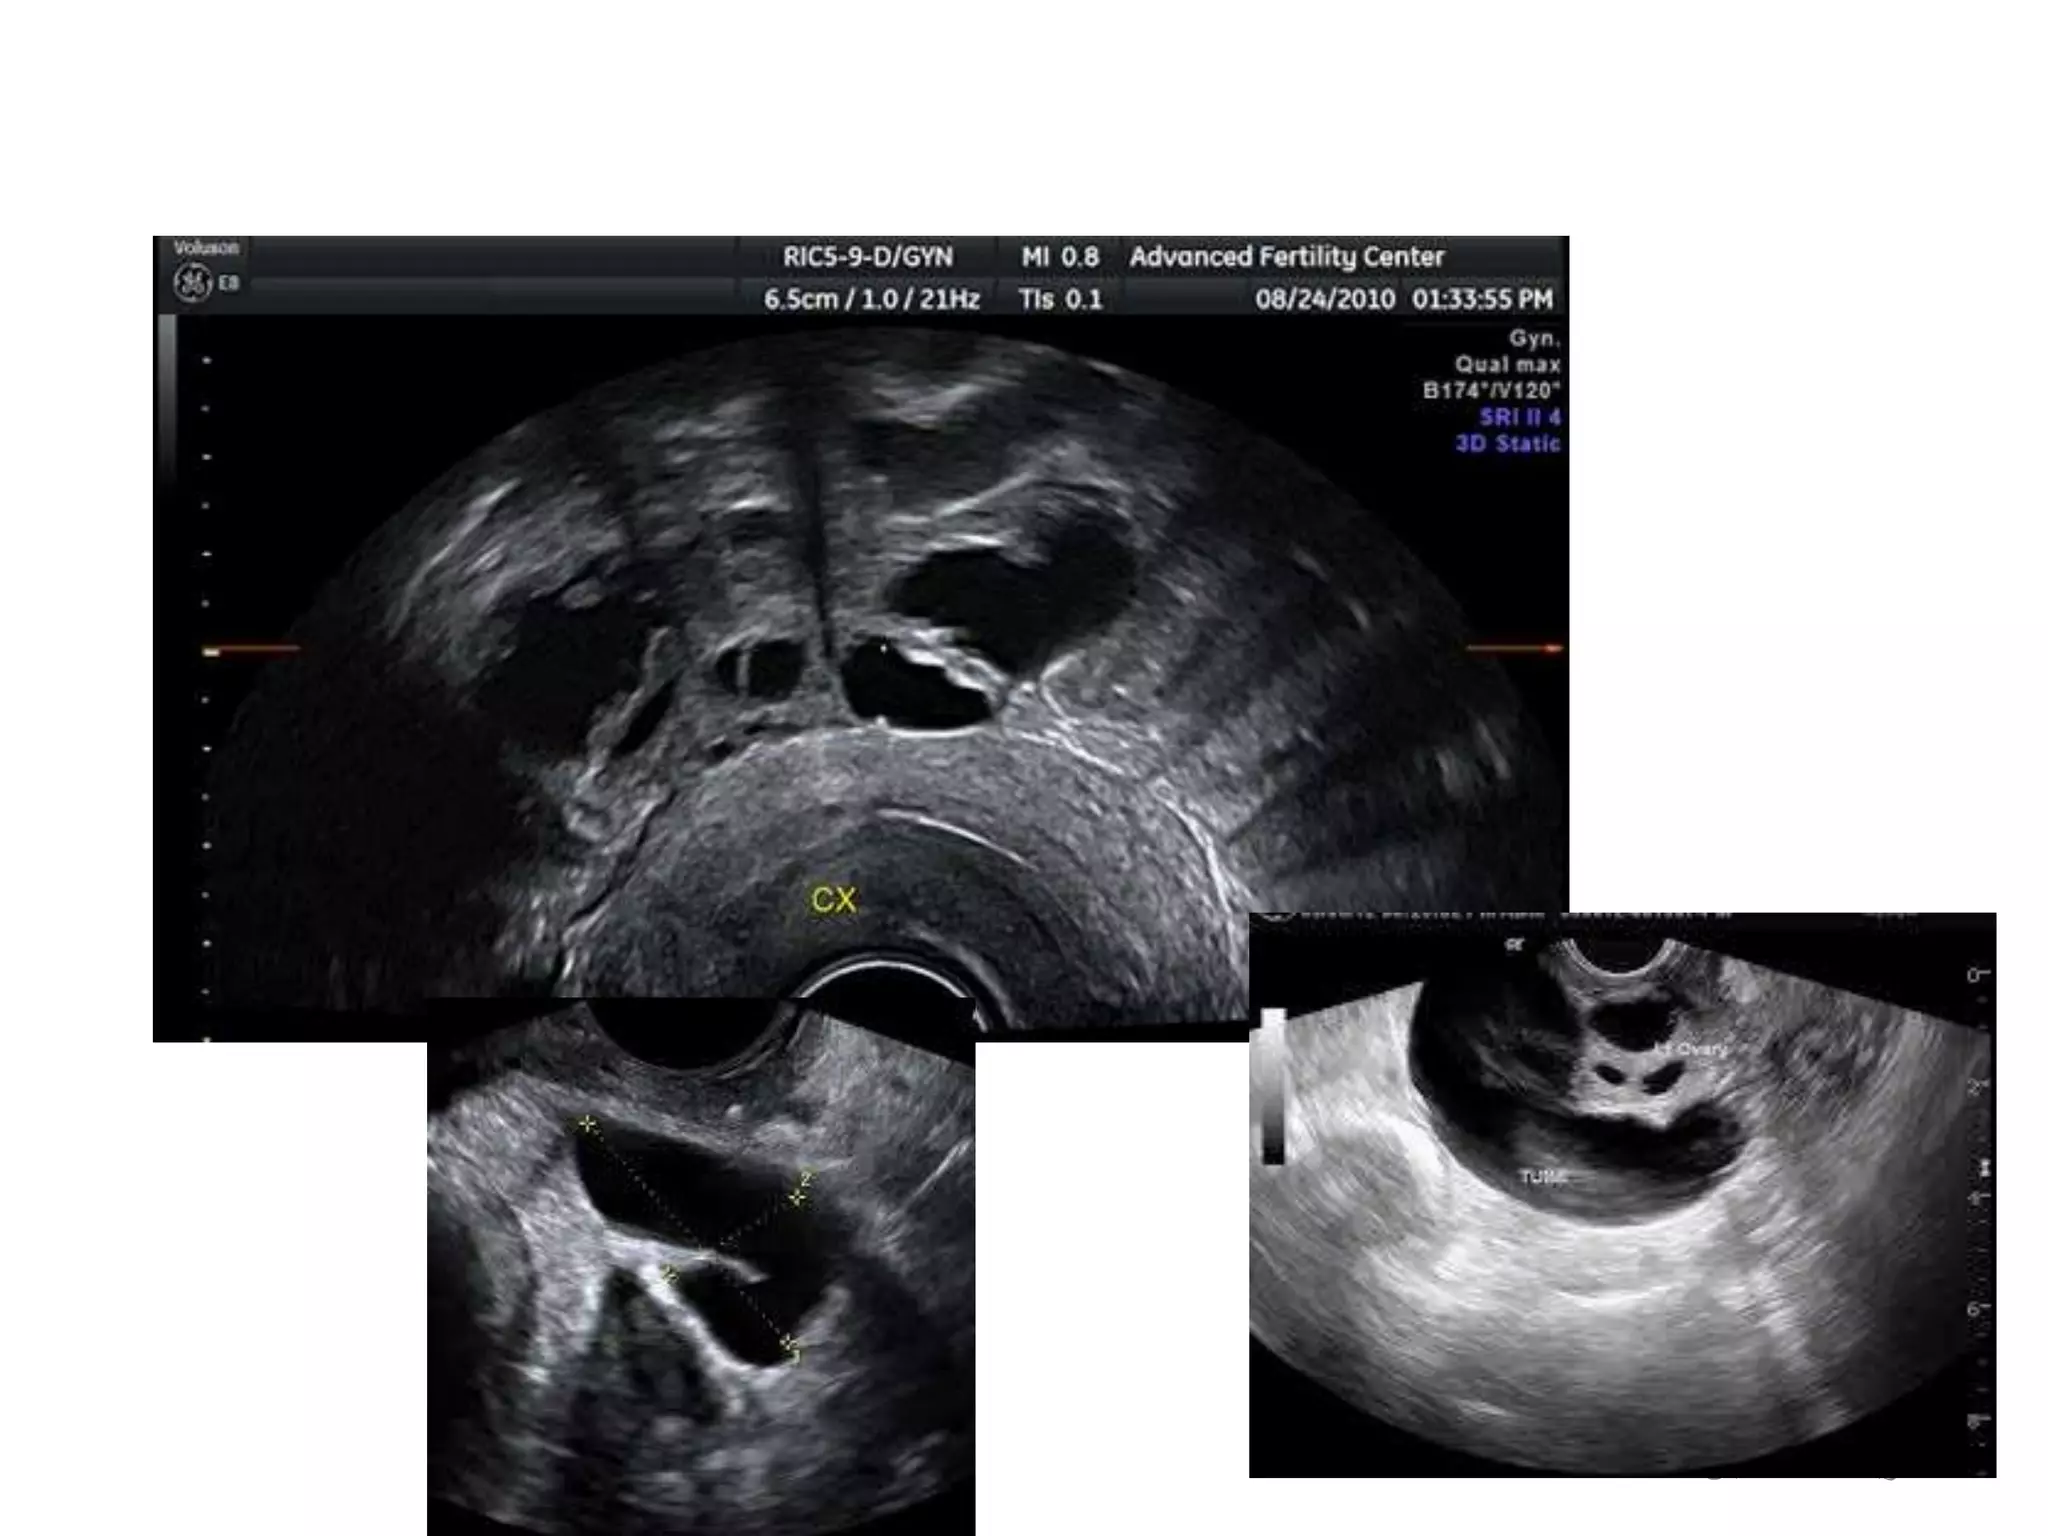

This document discusses reasons why IVF cycles may fail and provides guidance on learning from failed cycles. It defines recurrent IVF failure and recurrent implantation failure. Common causes of failure discussed include embryo quality, endometrial factors, and uterine issues like polyps or hydrosalpinx. Investigations like hysteroscopy and salpingectomy are recommended to address correctable causes. Other potential factors explored are endometrial thickness, scratching, and refractory endometrium. The goal is to identify avoidable causes and improve outcomes in subsequent cycles.